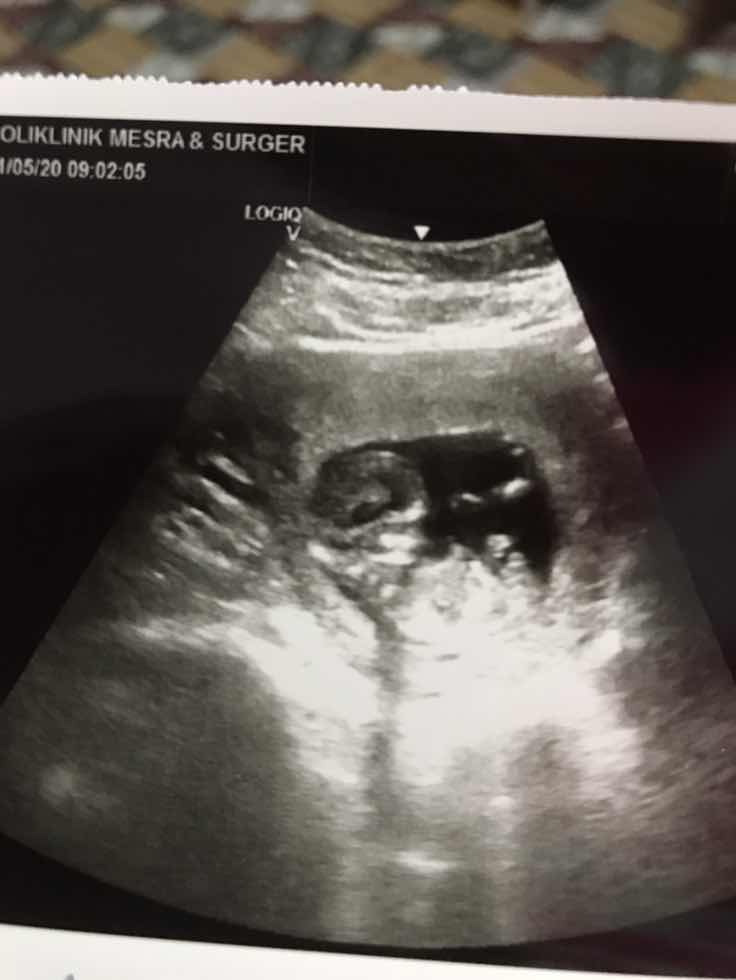

Mnta tlg mmy brpa weeks dpt scan gender

Hoping for a child

25 Weeks ke atas puan 😊